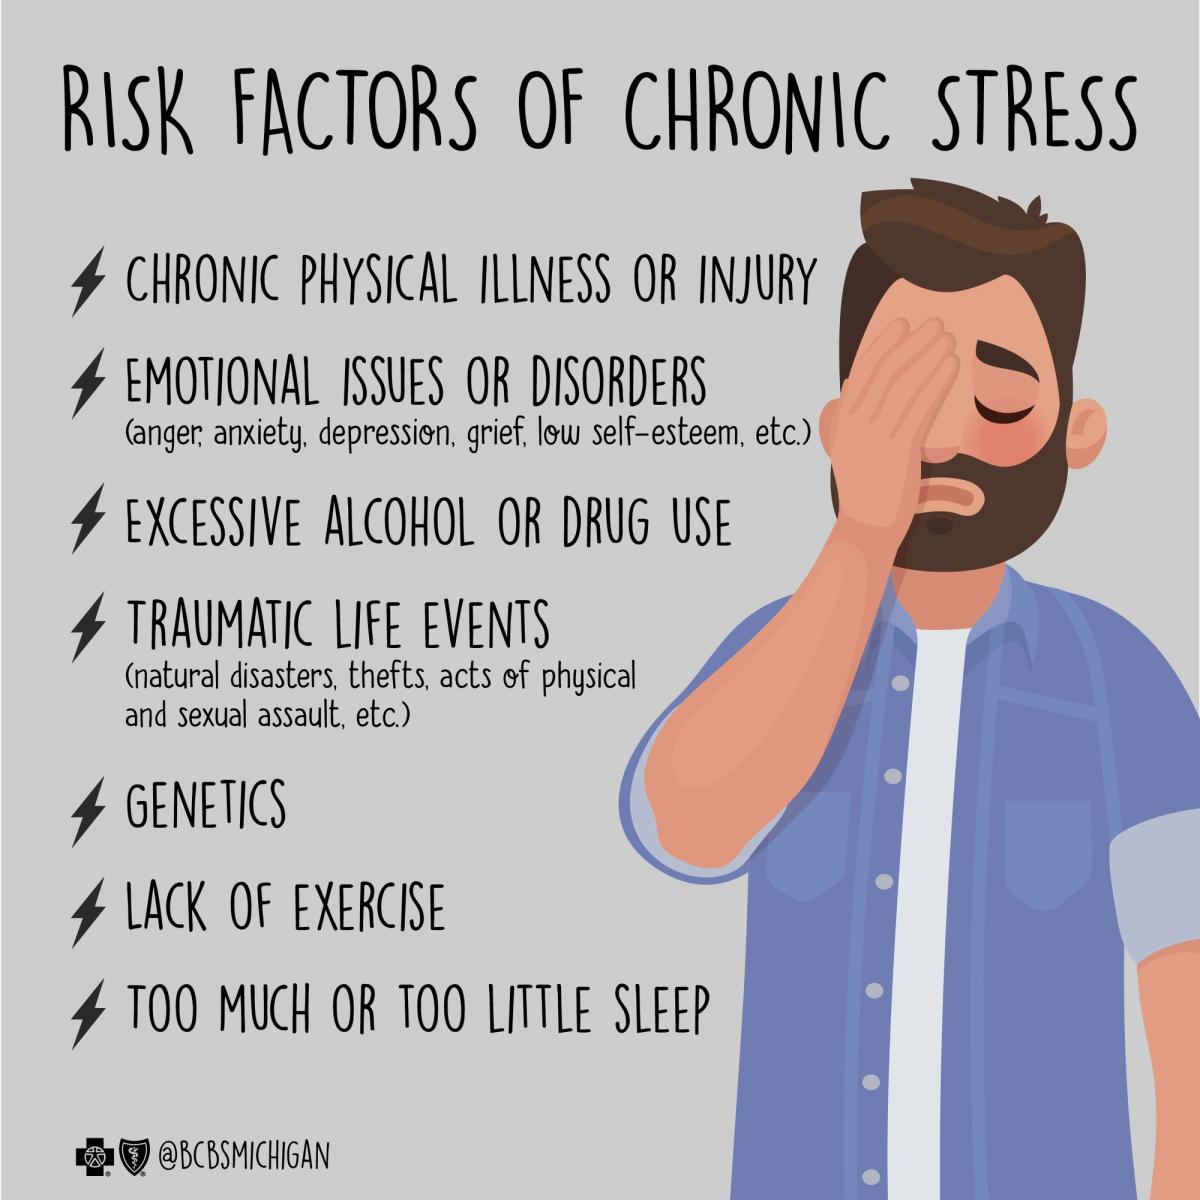

Research indicates that exposure to constant stressors, particularly in the form of constant news coverage, can lead to the development of news-related stress. This anxiety can manifest physically and emotionally, affecting both mental and physical health. While it's natural to care deeply about global issues, chronic exposure without relief can result in anxiety, depression, and decreased productivity.

Chronic stress has been linked to a range of physical issues, including increased blood pressure, heart rate, and inflammation. Over time, these physiological responses can increase the risk of heart disease and heart failure, menopause symptoms, and more. The link between chronic stress and skin conditions such as eczema, acne, and psoriasis highlights the ripple effect of chronic stress on human health.

Research suggests that chronic stress can cause changes in neural connections in various parts of the brain, including the hippocampus, prefrontal cortex, and amygdala. This shift can increase anxiety, cause memory loss and changes in learning and memory, and influences decision-making. These changes can be associated with a heightened state of alertness, designing a significant impact on daily routine.